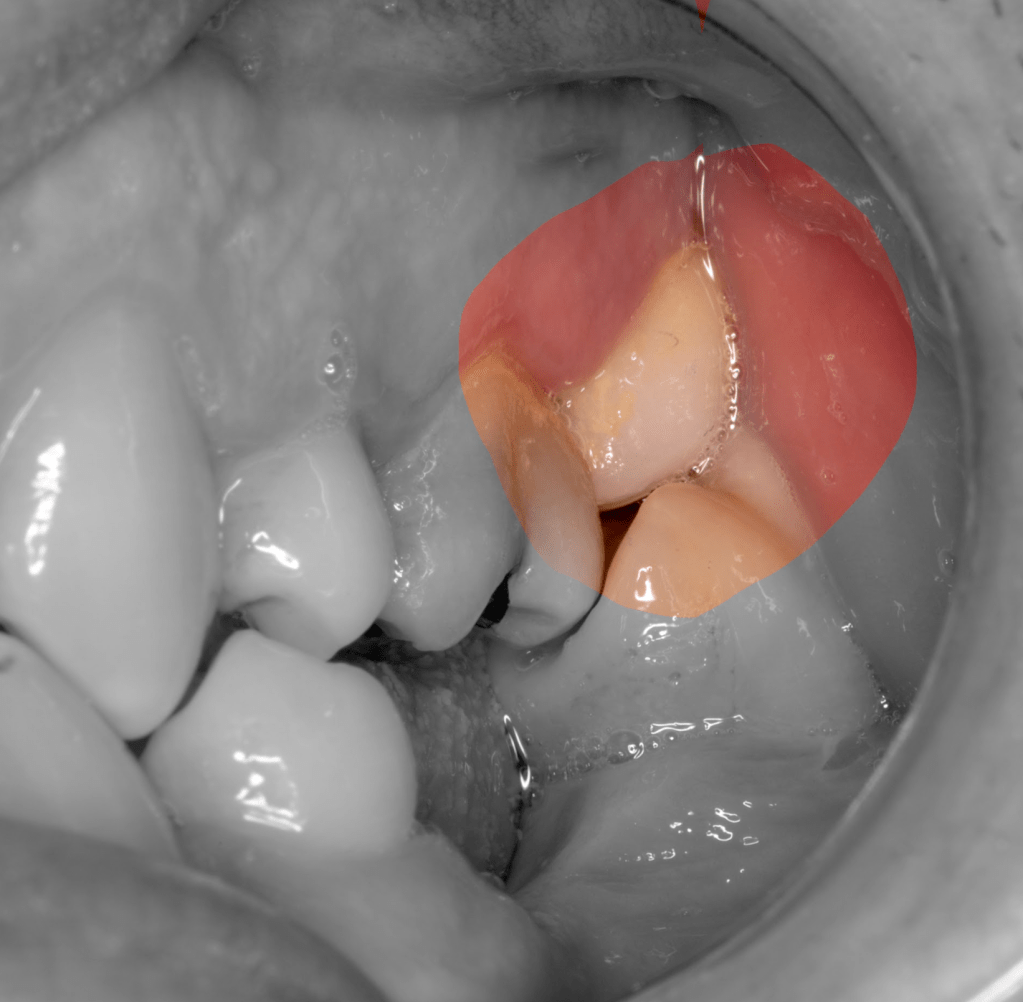

Diagnóstico de fisuras y fracturas

Diente fisurado regeneración total

Diente fisurado, no tratable

Diente fisurado tratable

Diente fisurado tratable con endodoncia

Diente fisurado tratable endodoncia 2

Fisura, remoción amalgama para explorar

Fractura cuspídea tratable

Vertical root fracture